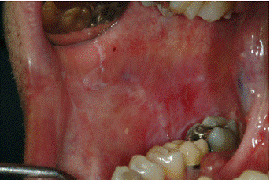

POST OP AFTER SIX MONTHS

ERYTHROPLAKIA